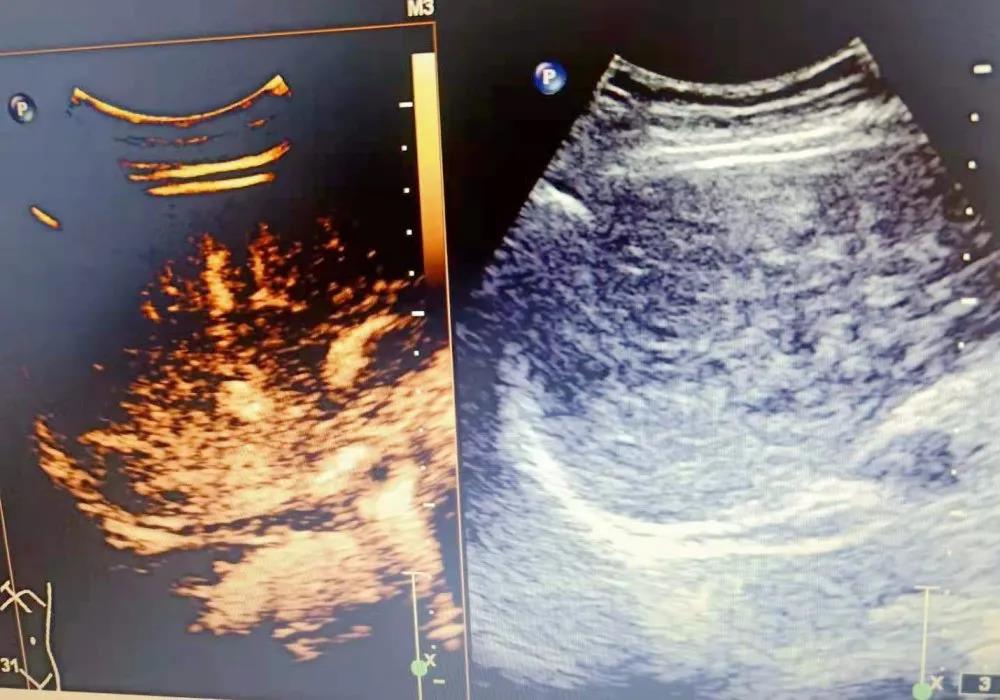

(超声造影成像)

超声造影作为目前最先进的超声成像技术,能无创、实时的反映病变的微循环血流灌注,它能提供比普通超声及彩色多普勒超声更丰富、更明确的诊断信息。它在常规超声检查的基础上,通过肘静脉注射超声造影剂,来增强人体的血流信号,实时动态地观察组织的微血管灌注信息,以提高病变的检出率并对病变的良恶性进行鉴别,整个检查过程便捷迅速,约10分钟左右即可完成检查,是一项无创、实时、无电离辐射、安全有效的新型影像学技术。

01超声造影技术优点:安全性好、无过敏反应、无射线、全程实时动态观察、检查费用相对较低。

02超声造影领域:可应用于临床多个领域,如消化系统、泌尿系统、妇科系统、心血管系统、浅表器官等,具体如下: